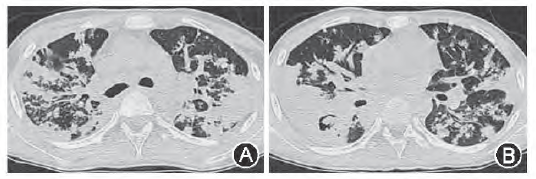

病例2:男34岁,抗HIV抗体阳性,确诊实验阳性。CD4+T细胞:40细胞/ul(正常参考值:706~1 125细胞/ul),痰抗酸染色:++++。胸部CT:双肺弥漫性粟粒影,右上叶前段、中叶有斑片样实变,主要为渗出性改变,同时存在血行播散性肺结核及继发性肺结核、淋巴结核。CT增强扫描淋巴结不强化或环形强化(图2)。

图2 胸部CT示双肺弥漫的粟粒影,右上叶前段、中叶有斑片样实变,主要为渗出性改变,同时存在血行播散性肺结核及继发性肺结核、淋巴结核。CT增强扫描淋巴结不强化或环形强化